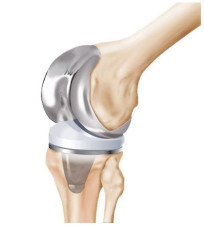

After years of legal maneuvering and court proceedings, the plaintiffs who filed product liability lawsuits against Zimmer Biomet regarding the defendant’s NexGen knee implant have agreed to a settlement arrangement. The news will likely be a huge relief to these plaintiffs, who have been waiting... Read More